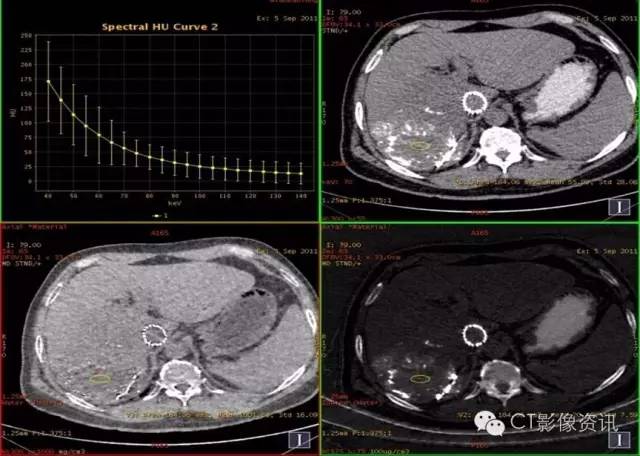

病史资料 男性,56岁,肝癌栓塞术后复查。

扫描参数 模式:GSI-22 375mA@0.7sec/rot@DC40mm@SFOV Body Large 螺距:0.984:1 平扫+增强扫描

静脉期:碘8.25,水1016.37

缩小ROI后放在病灶碘油未沉积区比较如下:

平扫:碘2.05,水1001.88

动脉期:碘1.66,水1009.80

结论:此例平扫、增强多期碘基物质定量无显著差异。栓塞治疗效果较好。

临床优势 肝癌栓塞后,因碘油和术后炎性反应的影响,短期内难以评估手术效果。通过能谱成像GSI分析,比较增强后碘含量与平扫时碘含量(有时可用水含量)的变化及变化趋势,来判断肝癌病灶是否还有强化,评估栓塞治疗的疗效和预后,并可指导临床进一步治疗。